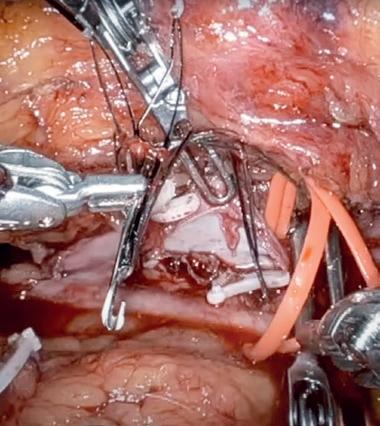

1. CTO of the left superficial femoral artery in a male patient suffering from severe claudication in the left calf

2. After subintimal passage, it was impossible to redirect the guidewire into the patent lumen distal to the CTO

3. Positioning of the BeBack catheter to re-enter the guidewire. Arrow indicates an orientation-marker

4. Marker appearing as a “C” indicates the direction of the needle, with the needle protruding maximally out of the BeBack catheter

5. An 0.018” guidewire passing into the patent distal lumen

6. Result after stenting